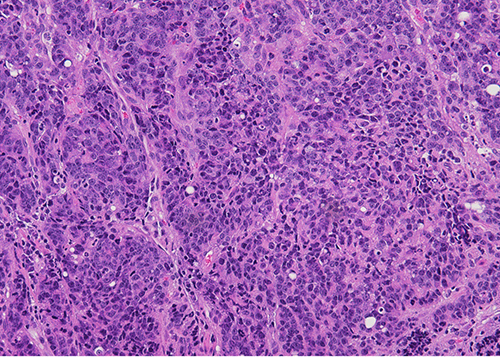

Figure 2 - High power view: Sheets of poorly differentiated malignant cells with admixed inflammatory cells (predominantly neutrophils).

Figure 3 - The neoplastic cells show amphophilic cytoplasm, nuclear enlargement, hyperchromasia, prominent nucleoli. Patchy neutrophilic infiltrate seen.

In this case, the histology showed sheets of poorly differentiated neoplastic cells with admixed predominantly neutrophilic inflammation. The neoplastic cells were positive for cytokeratins AE1/AE3 and CAM 5.2 consistent with carcinoma. They were diffusely positive for EBV by in-situ hybridization. DPC4/SMAD4, which shows loss of expression in approximately half of pancreatic ductal adenocarcinomas, showed retained expression. Immunohistochemical stains for mismatch repair proteins (MLH1, PMS2, MSH2, and MSH6) showed retained nuclear protein expression in the neoplastic cells. Immunohistochemistry for Her-2 was negative (score 0) and PD-L1 showed a combined positive score (CPS) of 5.

EBV was first identified in association with lymphoepithelial carcinoma of the stomach by Burke et. al. in 1990 (4). EBV-associated gastric carcinomas are often poorly-differentiated, consisting of irregular sheets, trabeculae, ill-defined tubules, or syncytia, and show prominent associated lymphocytic inflammation which may be intra- and/or peritumoral. In the 2019 World Health Organization (WHO) classification of digestive tumors, tumors with this morphology are categorized within the morphologic subtype of gastric carcinoma with lymphoid stroma (6). However, the morphologic spectrum EBV-associated carcinoma is variable and they may also show conventional tubular/intestinal adenocarcinoma morphology (5,7). Interestingly, our case showed intratumoral inflammatory cells, but they were predominantly neutrophils rather than lymphocytes. Positivity for EBV is typically established by in-situ hybridization by detection of positive signals within tumor cells.